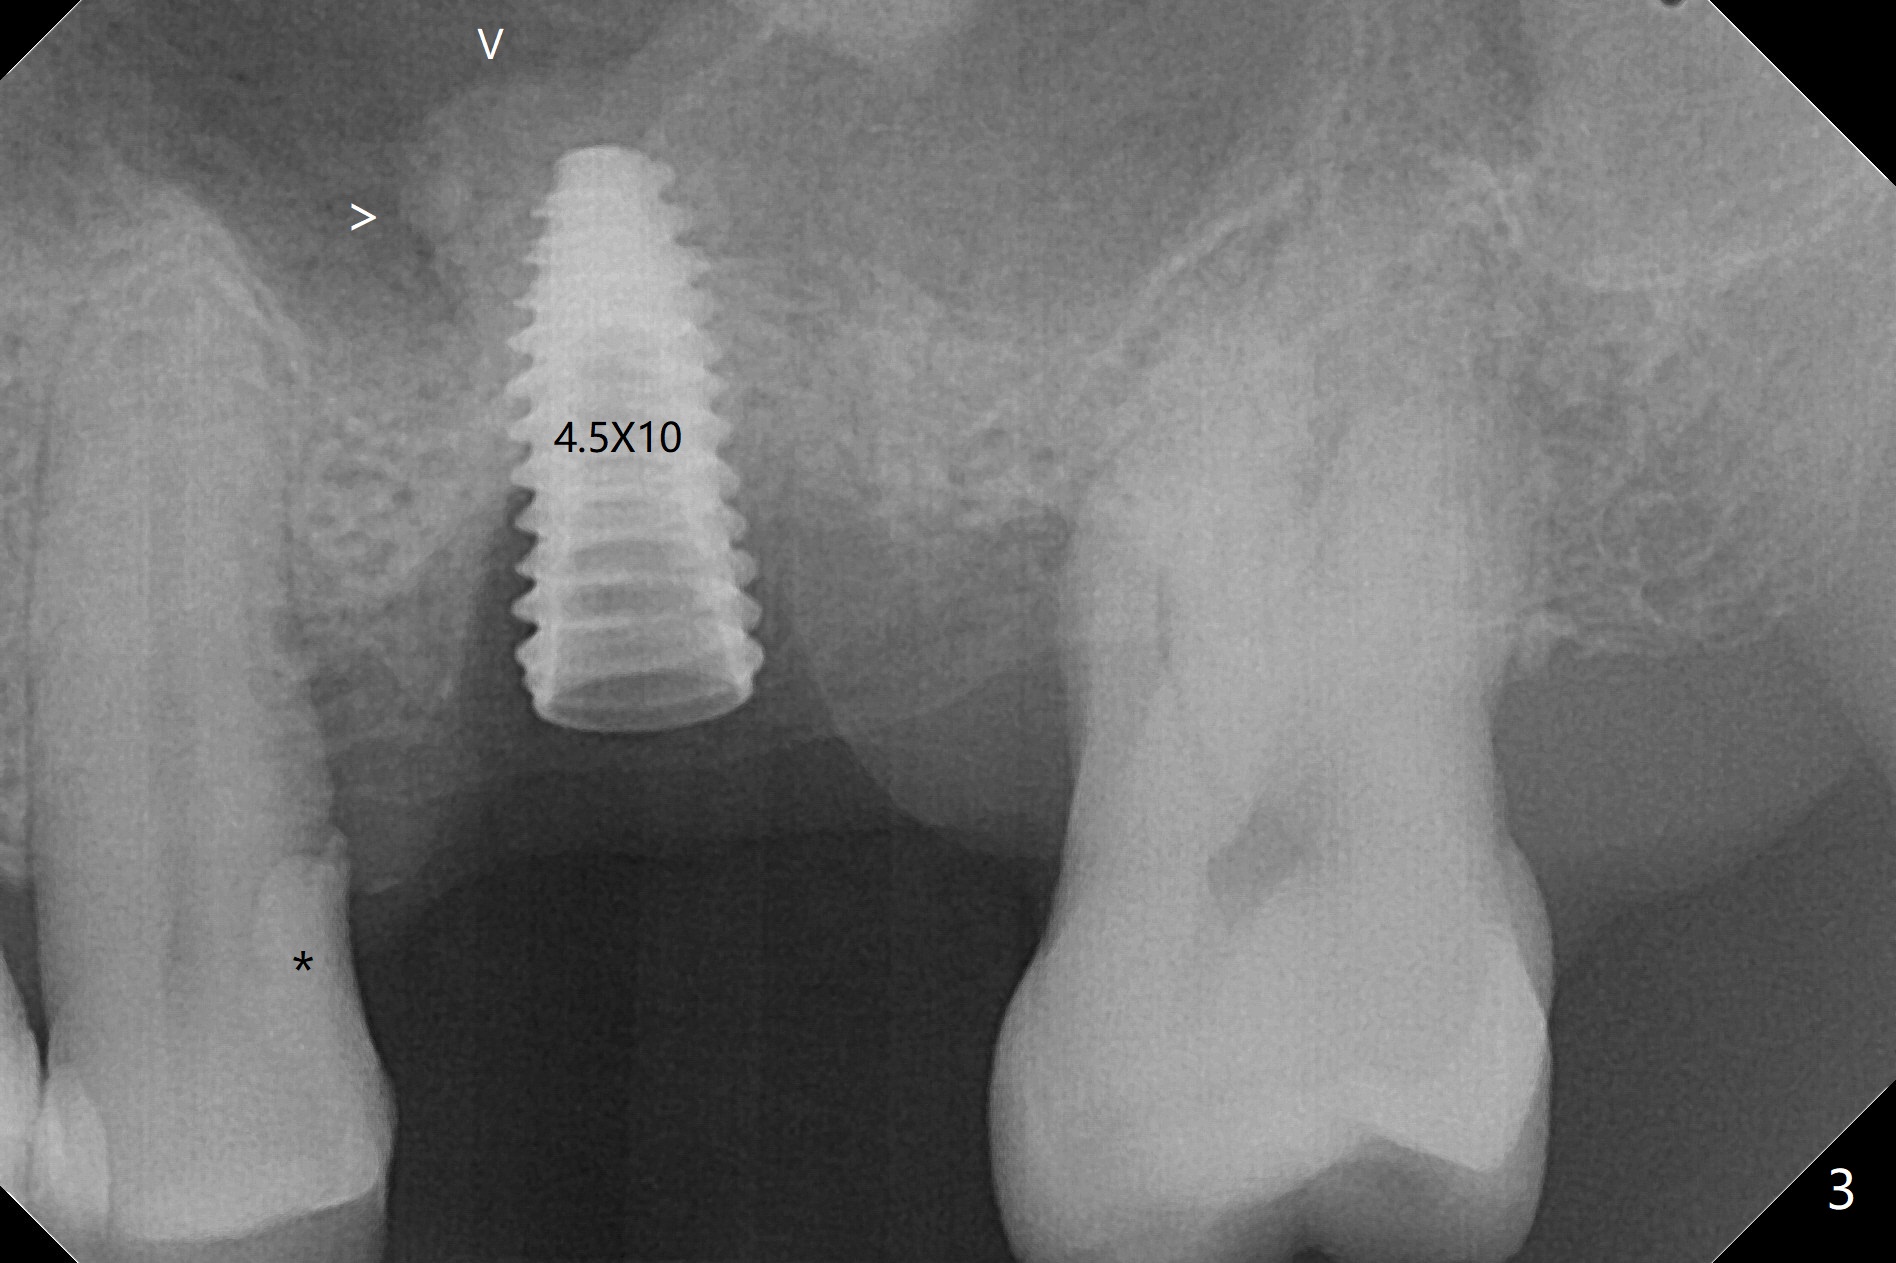

72岁男14号牙腭侧根尖接近上颌窦(图一,二:P),牙齿拔除后,根尖对刮治敏感,冲洗后,开始导板钻洞,圆钻穿透窦底,放置粘性骨粉和报废植体提升(图三:箭头)。放置小张PRF和骨粉(图四:箭头),植入正式植体,基台和骨粉(图五:*),最后覆盖PRF(图六),为了防止骨粉从邻牙牙龈沟(>)丢失,覆盖树脂敷料。基台和前后邻牙使树脂敷料术后一周巍然不动(图七:A)。术后一个月撤除树脂敷料,牙槽窝已经愈合(图八)。再过两周牙槽窝上皮好像进一步成熟(图九),然后塞入一个龈线,制备临时牙冠。